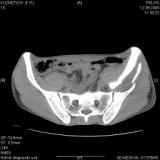

Уважаемые коллеги! Хотелось бы услышать совет по тактике лечения представлленого больного.Поступил после лечения в одном изотделений области. Травма 2,5 месяца назад. После выведенияиз шока был произведен остеосинтез перелома бедра, предплечья, до перевода к нам проводилосьвытяжение по оси шейки бедра за стержень, введенный в большой вертел. На сегодня деформацияригидна, клинически мобильности не определяется. Заранее признателен. P.S. Данный вид травм не включен в перечень "высокотехнологичных операций", направить длялечения по квотам Минздрава очень сложно.

Тяжелый случай... Поздняя реконструкция такого перелома технически сложное дело, вероятность осложнений,неуд.результатов выше(на PubMed article Johnson, Mast, Matta, Letournell results of acetabular reconstruction 20-120 days after injury).

Принимая во внимание обширность реконструкции, вероятность осложнений( остеоартроз, аваскулярный некроз), которые в любом случае должны будут решаться артропластикой сустава, пожалуй, я бы не стал оперировать сейчас: складывать мозаику многооскольчатого перелома, мобилизуя фактически сросшиеяся воедино фрагменты - дело травматичное с сомнительным результатом.

Привет, Леонид. Оскольчатый высокий двухколонный перелом в такие сроки трогать не надо, т.к. это про такие переломы сказано: "кто с ножом на Ж. пойдет тот в ней и останется...".